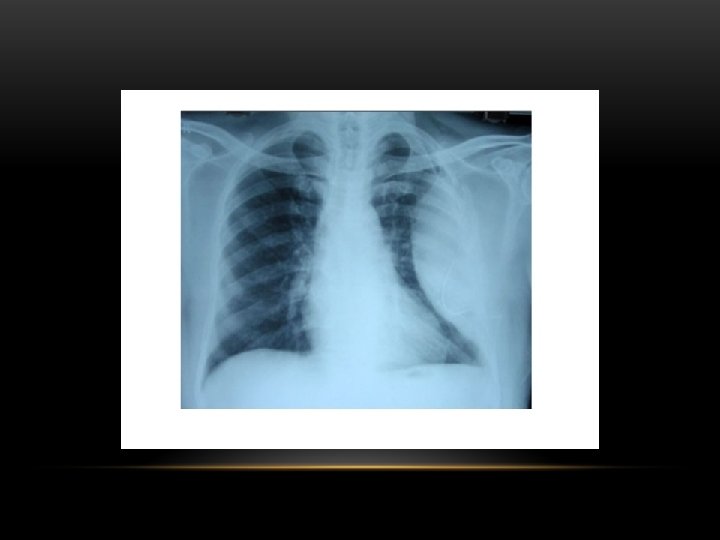

Tension pneumothorax : is the progressive build-up of air within the pleural space, usually due to a lung laceration which allows air to escape into the pleural space but not to return. Positive pressure ventilation may exacerbate this 'one-way-valve' effect. Progressive build-up of pressure in the pleural space pushes the mediastinum to the opposite hemithorax, and obstructs venous return to the heart. This leads to circulatory instability and may result in traumatic arrest.

Tension Pneumothorax • No vascular markings on right • Shift of mediastinum to left • Atelectasis right lung • Increased haziness on left: Diversion of entire cardiac output